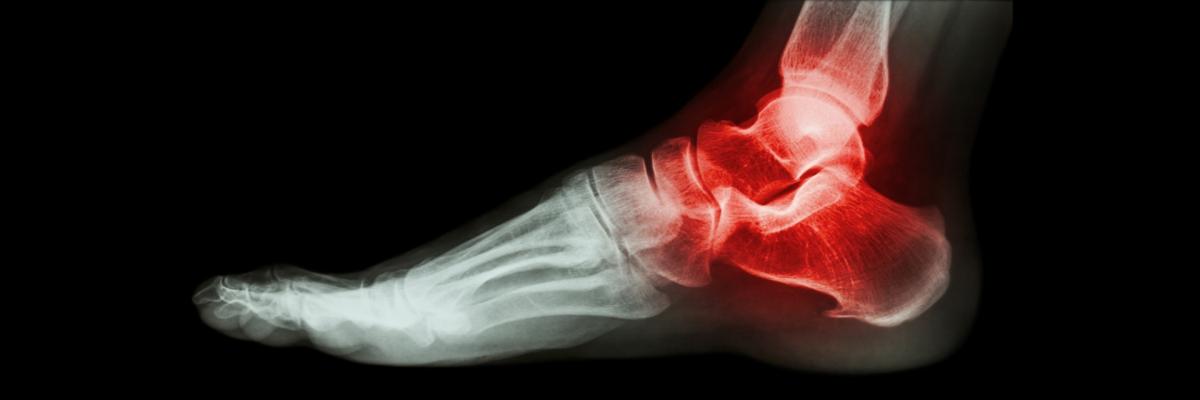

El Espolón Calcáneo es una afección que forma un exceso de material óseo en el hueso calcáneo del pie y que puede venir o no acompañado de dolor y de dificultad para caminar. Al ocasionar una tensión inadecuada en la fascia plantar, se produce tejido óseo en el talón, generando pequeños desgarros en la inserción del tendón.

El dolor presentado por el Espolón Calcáneo puede aparecer con mayor intensidad al momento de levantarse de la cama o al realizar actividades deportivas.